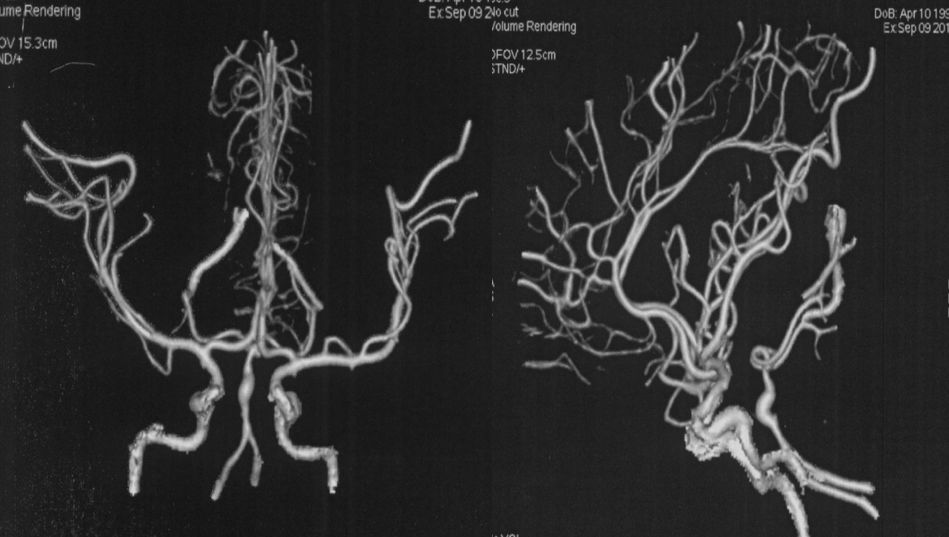

当地医院 CTA:基底动脉中上段瘤样扩张(图2)。

图2

当地医院DSA:基底动脉中上段夹层动脉瘤(2019-09-10)(图3)。

图3

本院DSA:基底动脉巨大夹层动脉瘤,双侧后交通动脉未见明显开放(图6)。

图6

本院 DSA三维血管重建(2019-10-10)显示:基底动脉巨大夹层动脉瘤(图7)。

图7